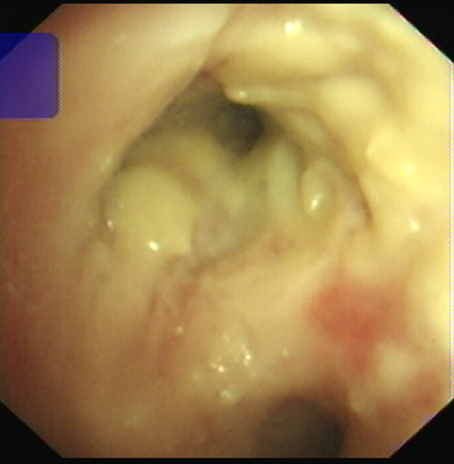

RICU陈泓主任医生阅读胸部CT,结合李女士呼吸道病毒检测提示**,根据多年临床经验指出李女士极有可能是流感后继发侵袭性肺曲霉菌病,果断经验性抗曲霉治疗,次日为李女士安排了床边气管镜检查,气管镜下见支气管管腔大量的白色膜状赘生物,管腔狭窄,它们如同顽固的藤蔓,紧紧缠绕着呼吸的通道。

▲气管镜下支气管黏膜覆盖大量脓苔,管腔狭窄

随后的支气管肺泡灌洗液GM试验、真菌培养、基因测序(mNGS)及支气管黏膜活检均指向了同一个致病菌:烟曲霉。

由于曲霉侵袭气管支气管导致管腔狭窄、管腔内大量膜状赘生物,李女士喘憋症状明显,每天要咳出大量黏痰,而且咳痰费力,RICU医护团队为她制定了周密的治疗计划:保持呼吸道通畅,加强痰液引流是关键,机械振动排痰、气管镜吸痰是必选项;主打的抗曲霉治疗既有静脉的输液治疗,也有气道吸入治疗;间断交替的无创呼吸机及经鼻高流量湿化氧疗改善缺氧、缓解呼吸肌疲劳。